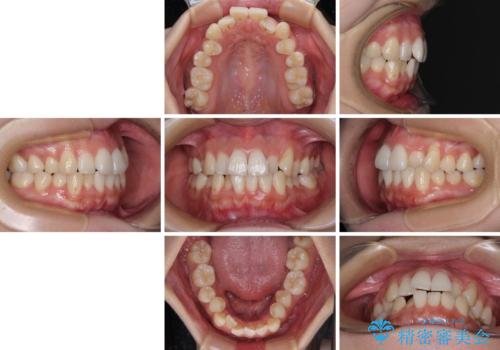

- 上下前歯のデコボコを気にして来院された患者様です。

上顎歯列が下顎の歯列に対して狭小であり、一部下顎の奥歯が上顎よりも外側に位置している状態でした。

上顎の急速拡大装置を使用して上顎骨を側方に拡大することで上顎歯列を拡大し、下顎歯列も拡大できるようにすることで、歯列を整えることとしました。

上顎の拡大は、左右どちらに拡大していくのか予想が困難ですが、こちらの患者様では結果として上下正中が一致する方向に拡大され、非常にきれいな仕上がりとなりました。